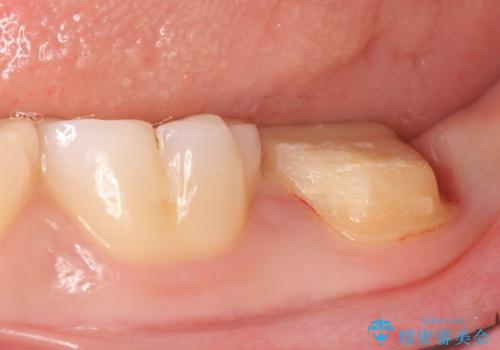

その後歯茎の治りを待ちポケットが正常値であることを確認後、オールセラミッククラウンによる補綴を行いました。

- オールセラミッククラウン…¥100,000、仮歯…¥10,000、歯冠長延長術…¥100,000費用は治療当時の料金となります